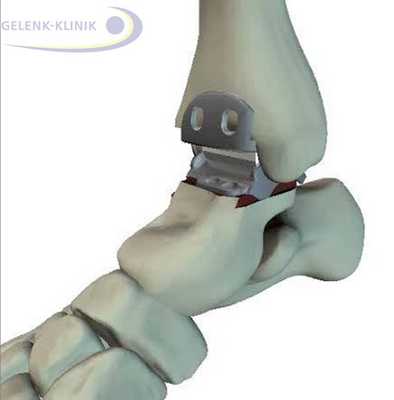

Артродез помогает восстановить безболезненность и потерянную подвижность. Данное вмешательство требует использования специальных винтов и интрамедуллярных гвоздей. Они фиксируют сустав до полной оссификации. © Gelenk-Klinik

Прочное важное для остеосинтеза костное соединение, закрепляется при помощи винтов либо пластин. Артроскопические вмешательства подразумевают лишь микроскопические разрезы на коже. Сохранение мягких тканей является является важным элементов в таком лечении: только при низком рубцевании, в будущем возможно эндопротезирование.